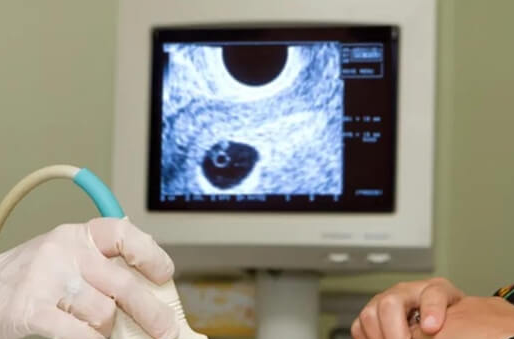

二、B超检查:确诊腹水的“金标准”

B超通过高频声波成像,可清晰显示腹腔内液体分布及量,是诊断腹水的核心手段:

定量评估:超声可测量腹水深度(如盆腔积液超过5厘米提示中度腹水),并观察是否合并胸腔积液。

动态监测:通过多次检查对比腹水量变化,指导治疗调整。

鉴别诊断:排除腹腔出血、感染等其他急症,确保诊断准确性。